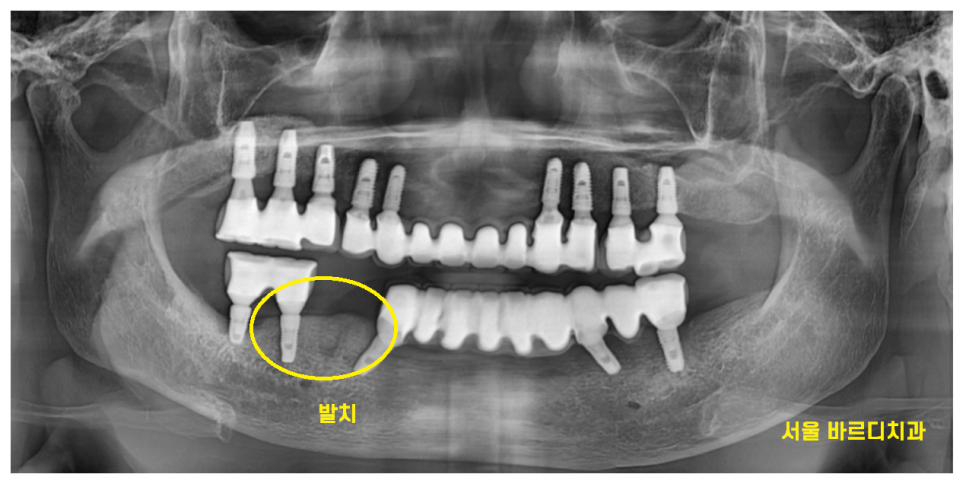

엑스레이 사진에서도 보이지만

치료를 참 많이 하신 환자분입니다.

전악 임플란트를 하셨고

남아있는 내 치아는 딱 2개

오른쪽 아래 작은 어금니만 본인 치아셨습니다.

보철 치아와 비교하였을 때

자연치아는 티가 나죠~?

아주 작은 충치가 있긴 하였지만

이정도는 관리만 잘해도 되는 수준

문제는..

뼈!!가 문제였습니다.